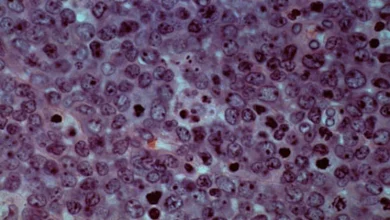

Fiscal and inflation worries are putting upward pressure on long-term interest rates across the G3, and these concerns are not going away anytime soon, see chart below.

The bottom line is that long-term interest rates are going to stay higher for longer and investors should plan accordingly.

Sources: US Department of Treasury, Macrobond, Apollo Chief Economist